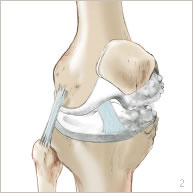

Le genou correspond à l’articulation entre le fémur et le tibia. La rotule est une troisième partie osseuse qui est située en avant et qui fait partie de l’articulation. Les surfaces articulaires de glissement sont recouvertes de cartilage (figure 1). De nombreux muscles et tendons entourent cette articulation et permettent d’étendre et de plier le genou. La stabilité du genou est assurée par des ligaments qui sont des sortes de rubans plus ou moins élastiques.

L’arthrose est l’usure du cartilage présent au niveau des surfaces de glissement. Cette usure s’accompagne aussi de remaniements de l’os sous-jacent. L’arthrose est partielle quand elle ne touche qu’une partie du genou (figures 2 et 5). Elle occasionne des douleurs ainsi qu’un enraidissement et une difficulté à la marche nécessitant l’utilisation importante d’anti-inflammatoires, d’anti-douleurs et parfois même d’une canne.

Une incision est réalisée au niveau de la partie antérieure du genou. Un passage est fait sur le côté de la rotule pour accéder à l’articulation. Le cartilage usé est enlevé. Le cartilage sain est préservé ainsi que l’ensemble des ligaments. La partie usée du fémur et la partie usée du tibia sont préparées (figure 3).